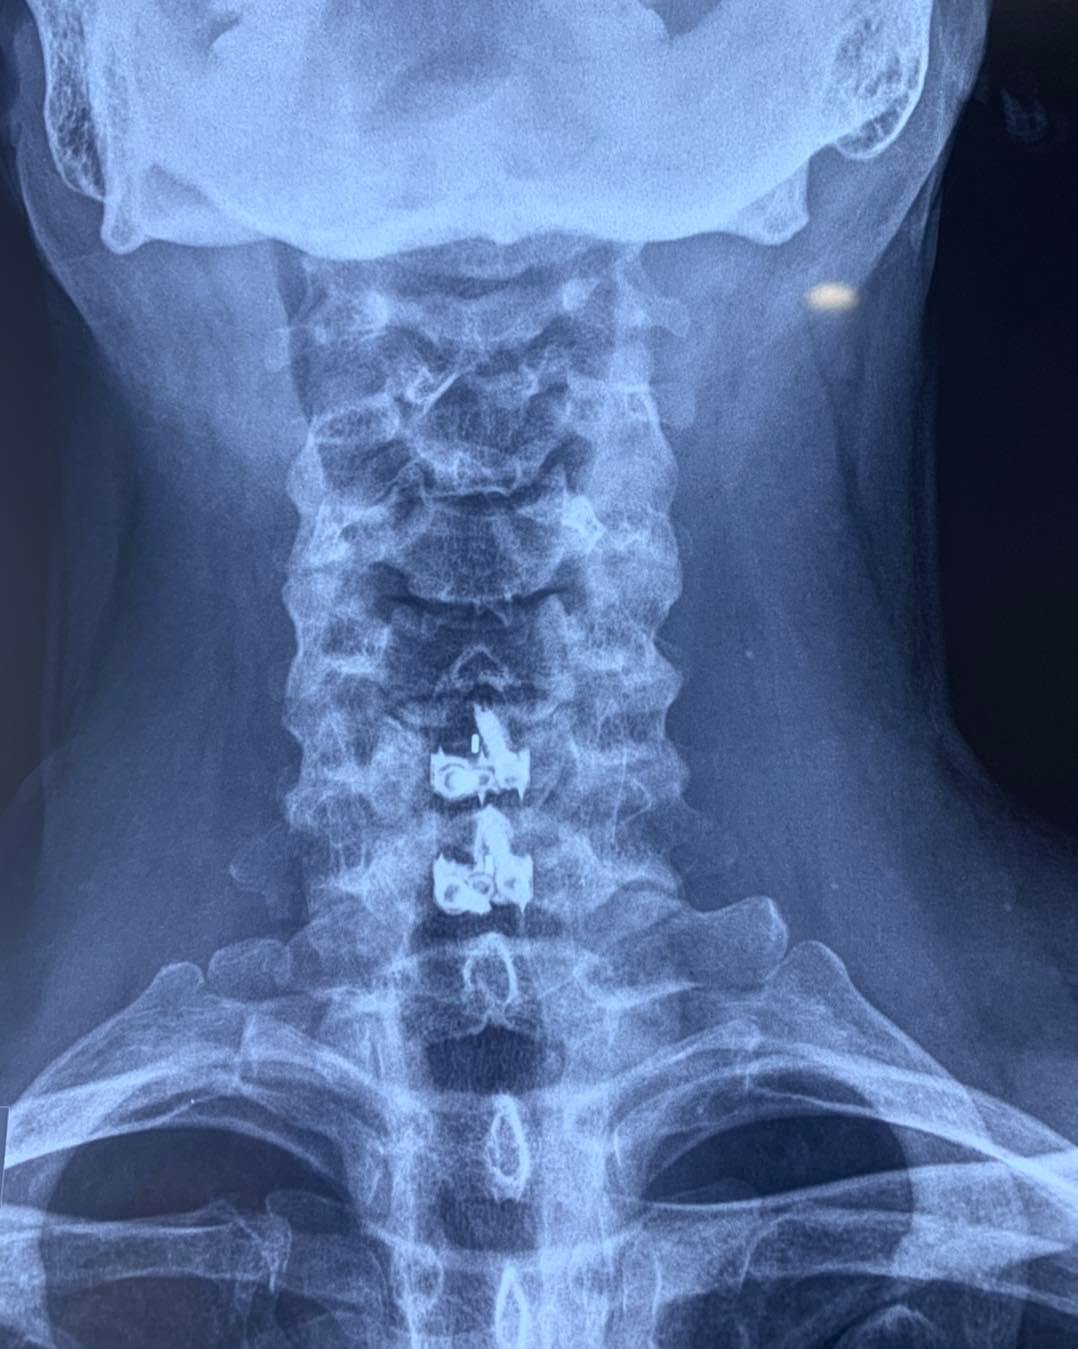

CIRUGIAS

RESULTADOS